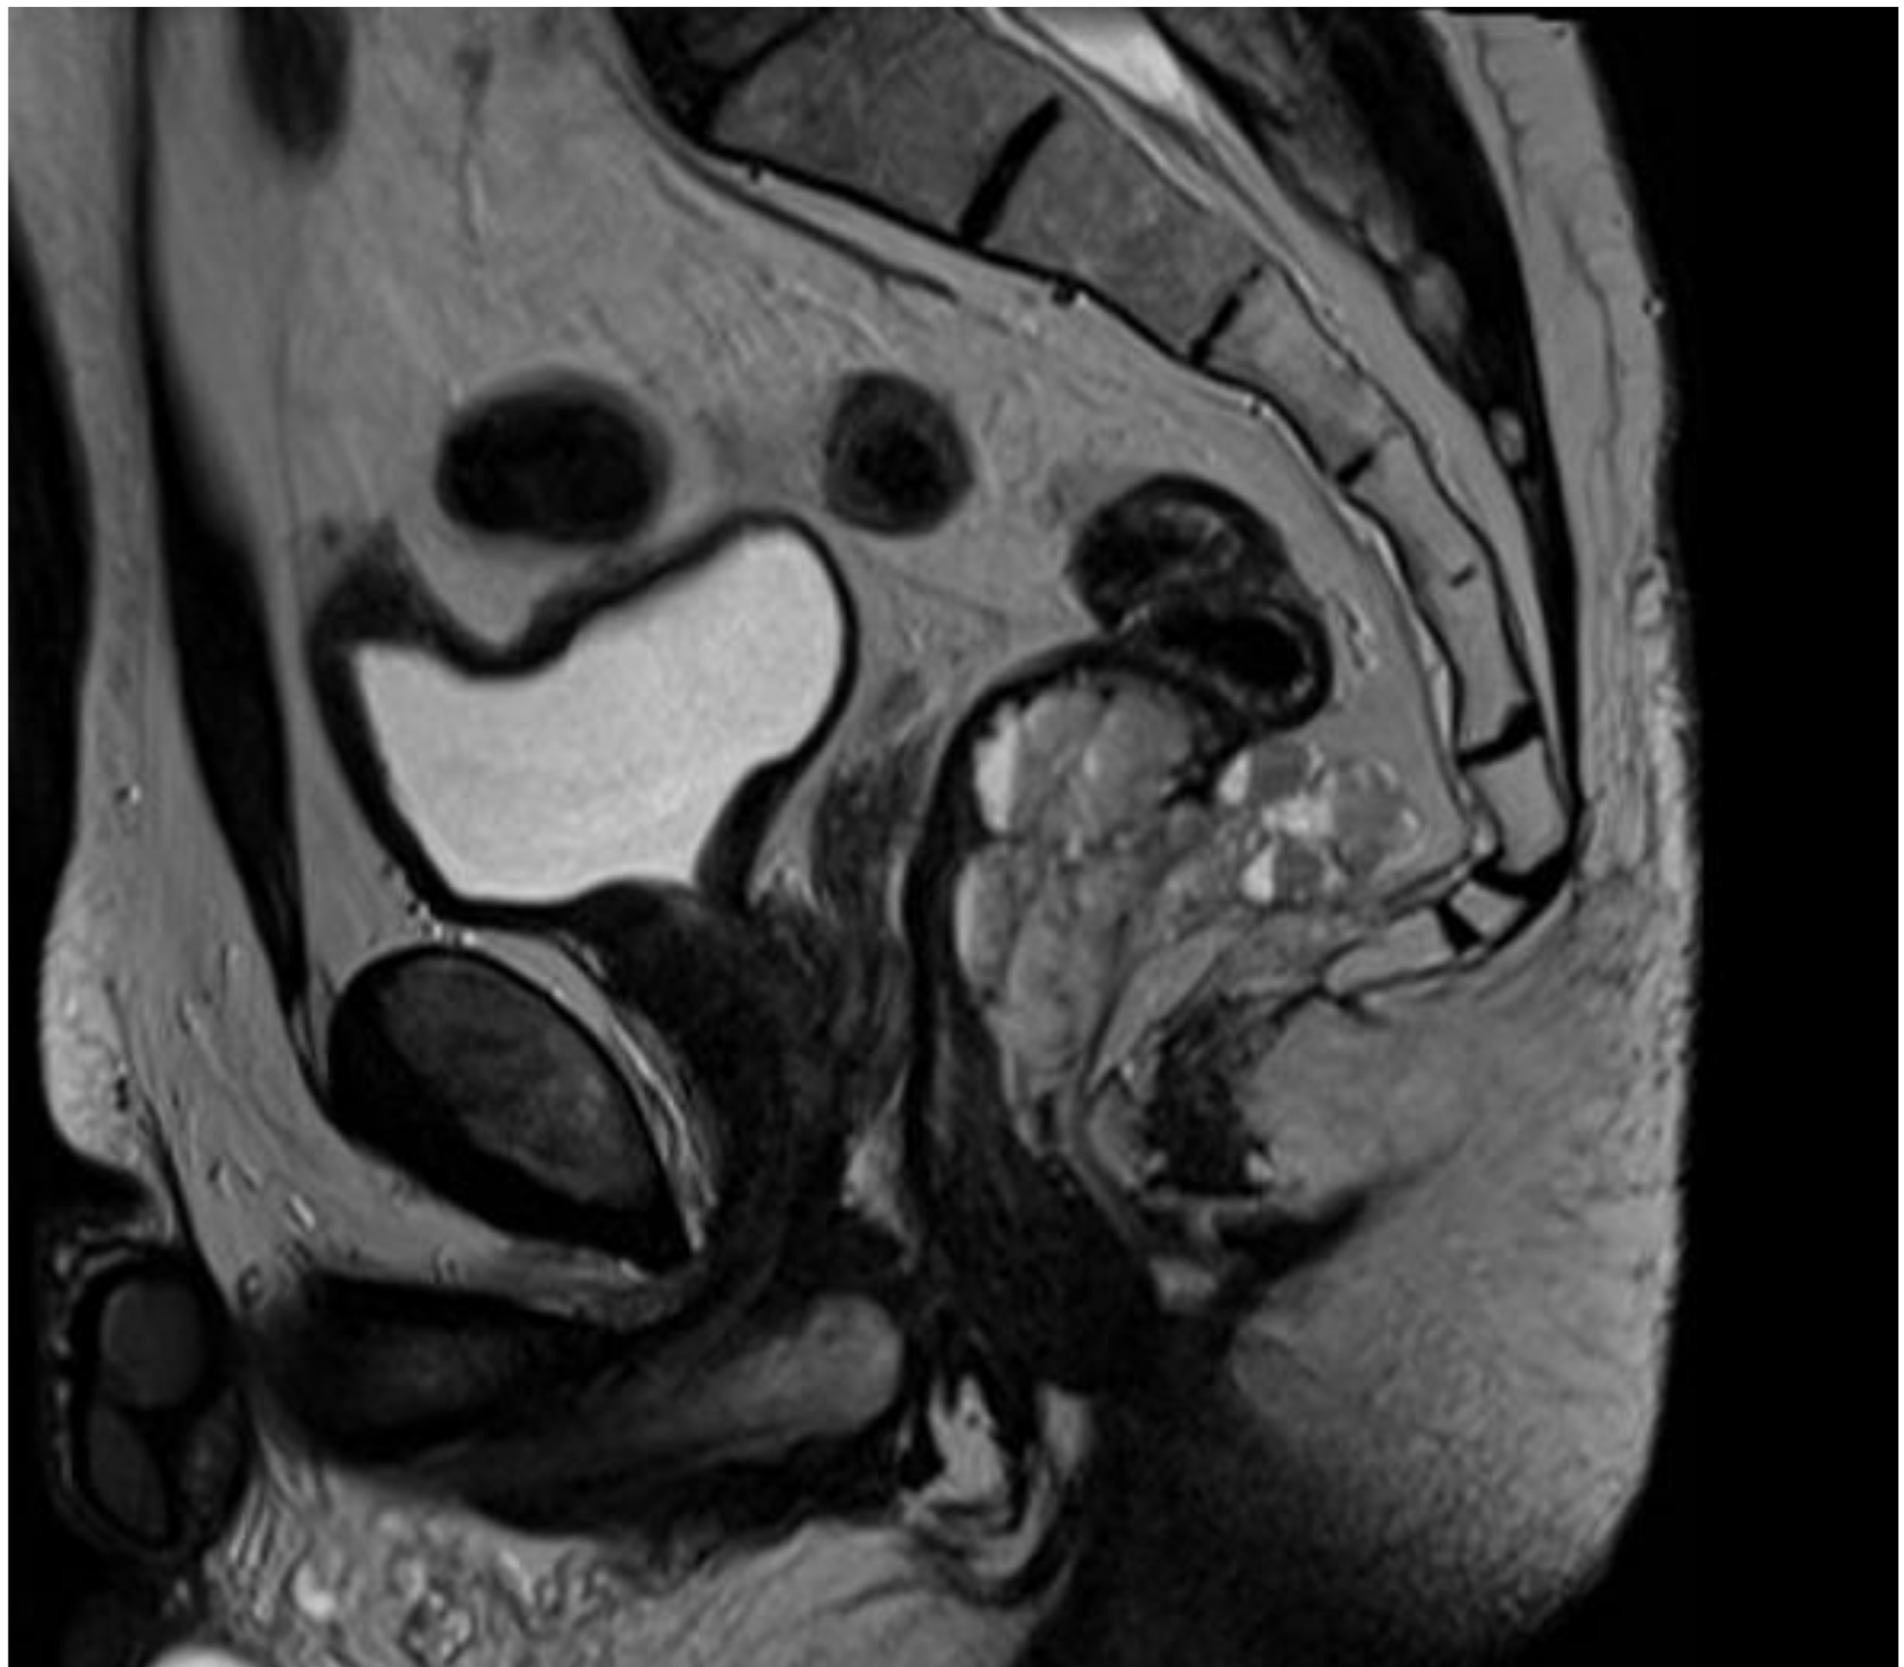

We report the case of a 52-year-old male patient in whom a vegetative lesion of the distal rectum was incidentally identified during urological evaluation for bladder carcinoma. The patient’s medical history was notable for episodes of hematochezia, which had not previously undergone proctological assessment. Endoscopic investigations were conducted (Figure 1); however, biopsy specimens yielded non-diagnostic results. Computed tomography (CT) imaging demonstrated apparent obliteration of the distal rectal lumen by a parietal mass measuring approximately 4 cm. To further characterize the lesion, contrast-enhanced MRI was performed, confirming the presence of an expansive mass in the distal rectum (Figure 2).